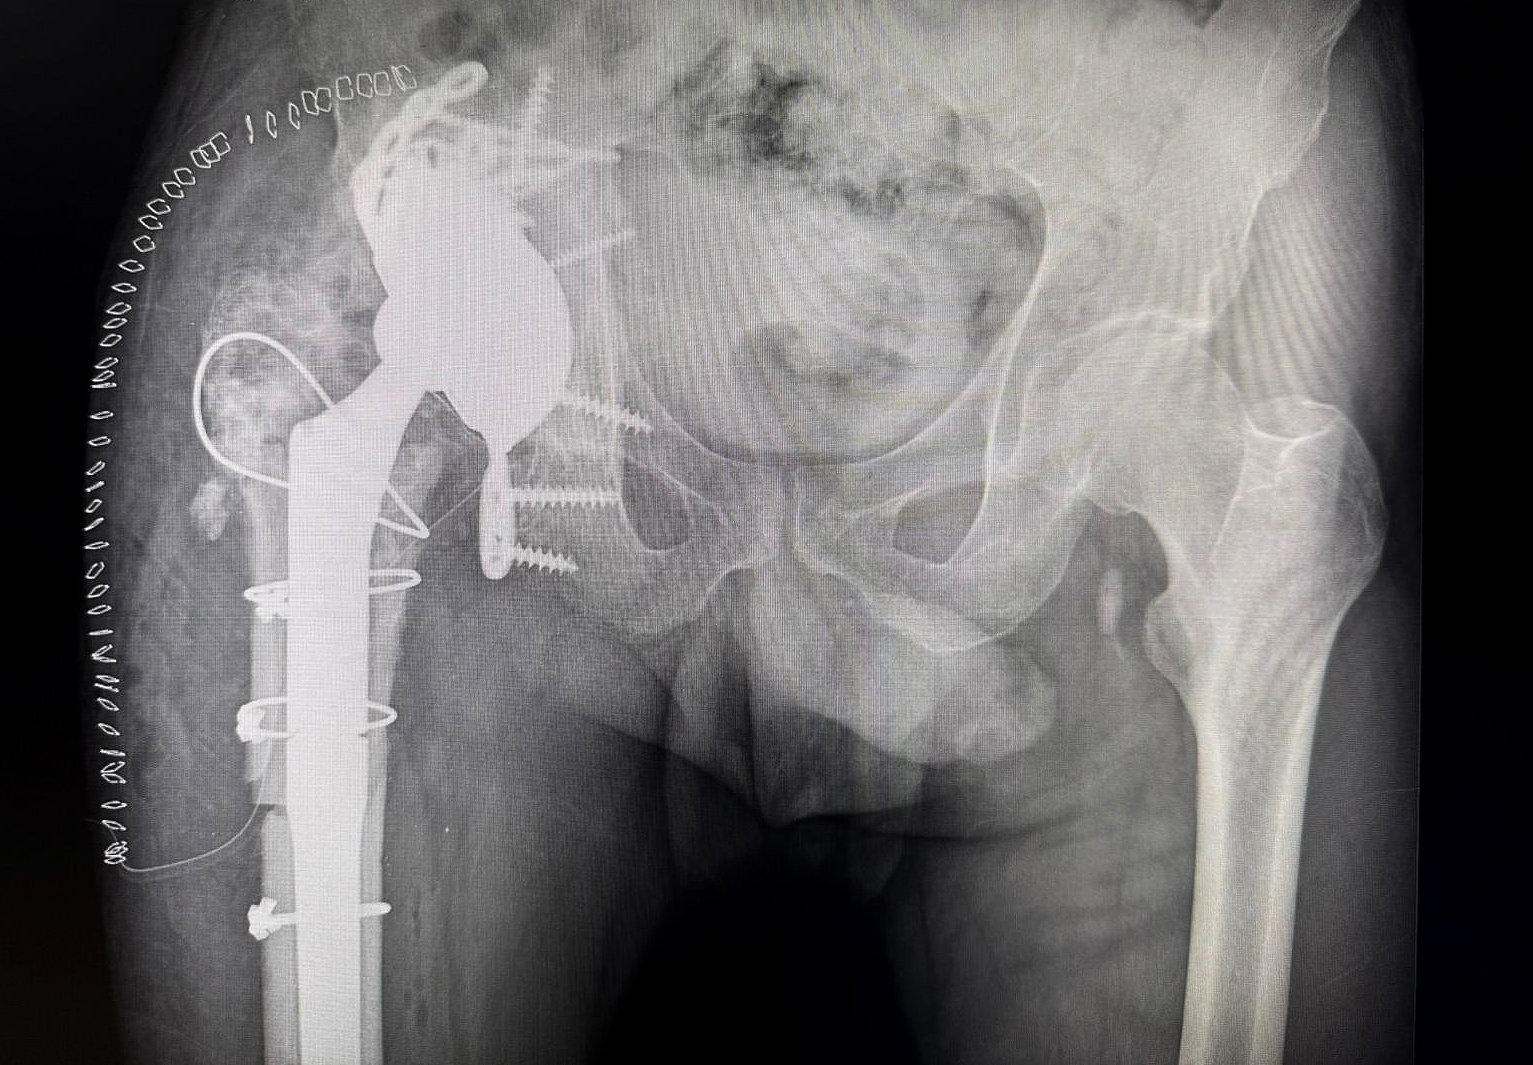

Preoperative X-ray demonstrating severe acetabular bone loss and loosening in a multiply revised right hip.

Plain radiographs demonstrated a loose acetabular component, severe acetabular bone loss, and heterotopic ossification.

Postoperative X-ray showing integrated augment–cage construct with stable fixation, allowing early full weight-bearing.

The extreme malleable flanges allowed the cranial fixation.

Off-the-shelf MobileLink PPR using a Dual Mobility Insert, combined with a TrabecuLink Augment.